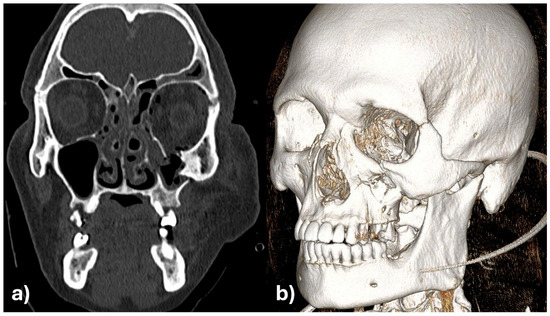

The initial assessment showed facial asymmetry, periorbital swelling, and diplopia. Clinical examination revealed depression of the zygomatic arch on the left side and restricted ocular movement. CT scan confirmed fractures of the zygomatic-maxillary-orbital-complex, with significant displacement of the zygomatic bone and herniation of orbital contents into the maxillary sinus (Figure 7a,b).

Figure 7. Zygomatic-maxillary-orbital-complex fracture of the left side in coronary view (a) and as 3D reconstruction (b).